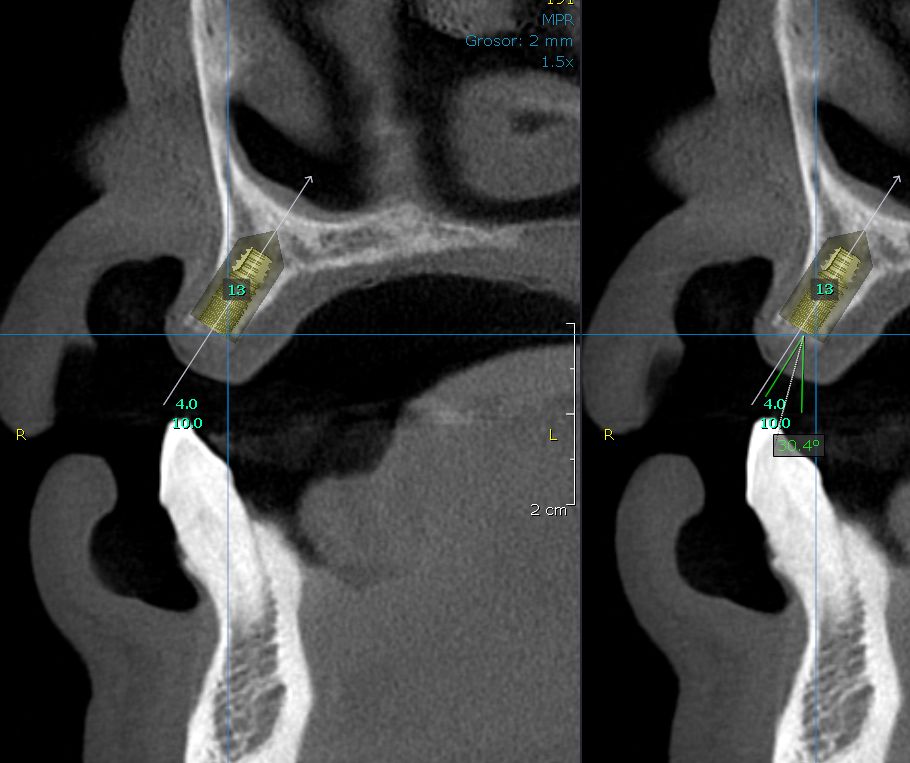

Un implante dental es la sustitución de un diente dañado por un tornillo de titanio para sostener una prótesis que simule el diente faltante, una de las técnicas que mas utilizamos en nuestra consulta es "flapless" lo que evita molestias innecesarias, reduce notablemente el dolor y la inflamación y permite la reincorporación a nuestras actividades cotidianas mas rápidamente, mientras se termina el resto del proceso.